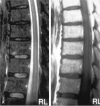

F<sc>ig</sc> 8.

Fig 8.

Another patient with intraspinal abnormalities. A, Sagittal T2WI shows abnormal increased signal intensity in the conus medullaris. B, Axial gadolinium-enhanced T1WI shows abnormal foci of enhancement in the conus medullaris. C, Axial T2WI shows markedly increased signal intensity in the thoracic cord. This is appreciated despite image degradation due to artifact.